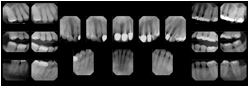

OO.1.4 Radiology

• A radiologist on his PACS assembles a screen layout of a stack of CT images of a current lung study, a secondary capture of a 3-D rendering of the CT, and a prior chest radiograph for the patient. He adjusts the window width / window level for the CT images, and zooms and annotates the radiograph to clearly indicate the tumor. He saves a Structured Display object representing that screen layout, including Grayscale Softcopy Presentation State objects for the CT WW/WL and the radiograph zoom and annotation. During the weekly radiology department conference, on an independent (non-PACS) workstation, he accesses the Structured Display object, and the display workstation automatically loads and places the images on the display, and presents them with the recorded WW/WL, zoom settings, and annotations.

• A mammographer reviews a screening exam on a mammo workstation. She wishes to discuss the exam with the patient's general practitioner, who does not have a mammo-specific workstation. She saves a structured display, with presentation states for each image that replicate the display rendered by the mammo workstation (scaling, horizontal and vertical alignment, view and laterality annotation, etc.).

Mammography Structured Display

Figure OO-7. Mammography Structured Display